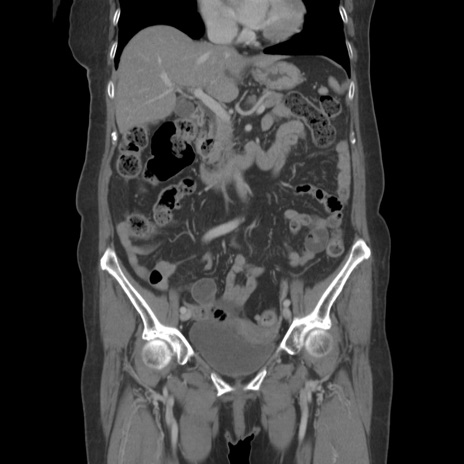

横断像

【症例】80歳代女性

【主訴】下腹部痛

【現病歴】約8時間前より下腹部痛の出現あり、救急外来受診。

【既往歴】両側付属器切除

【身体所見】意識清明、下腹部正中に手術痕あり、その部位に一致して圧痛と反跳痛あり。腸蠕動音は亢進。

【データ】WBC 9300、CRP 0.15